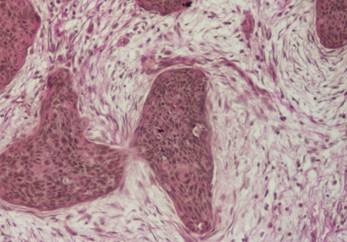

Figura 2: Carcinom cervical microinvaziv timpuriu.

Placarde de celule tumorale înconjurate de fibre colagene tinere fuxin-negative.

Tricrom van Gieson x 100

Figura 3: Carcinom cervical invaziv, reactie stromala evidenta, fibre colagene groase,

HE x 100

Evaluarea semicantitativa pe care am efectuat-o lotului intrat în studiu demonstreaza intensificarea maturarii fibrelor colagene ce devin fuxinofile, în special în cazul formelor invazive de carcinom scuamos al colului uterin.